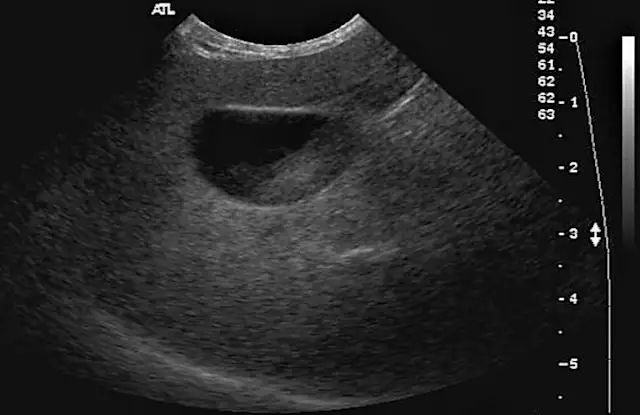

FIGURE 1

A male dog with hyperadrenocorticism, with classic alopecia and a pendulous abdomen. Photo courtesy of Dr. Anthony Yu